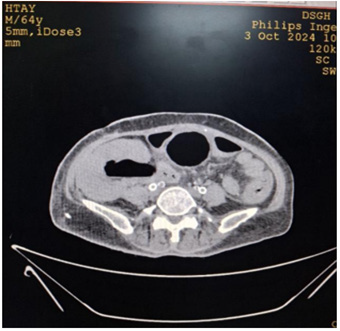

Cystoscopy was done to detect mucosa lesions in bladder; the whole mucosa was congested and red. There were multiple hemorrhagic areas in whole bladder mucosa; it was bled on touch. There was no focal ulcer or tumor. Therefore, generalized congested mucosa, hemorrhagic areas were probably due to DIC or CMV cystitis or candida cystitis or bacteria cystitis. The color of urine coming from Vescio-ureteric orifice of graft kidney was clear. Hemostasis was done with Ball electrode; bladder wash out was done with Tomey’s glass syringe. Figure 9-15 reveal cystoscopy findings. Abdominal tomogram was done; it revealed a swollen allograft kidney with air in the renal pelvis and renal vessels and subcapsular area suggestive of emphysematous allograft pyelonephritis. And, air along bladder wall was seen indicating emphysematous cystitis. They are illustrated in (Figure 16-19).

Figure 16: CT abdomen axial view non-contrast showing swollen allograft kidney with air in the renal pelvic.

Figure 17: CT abdomen coronal view non-contrast showing swollen allograft kidney with air in the renal pelvic, subcapsular area and air along bladder wall.

Figure 18: CT abdomen coronal view non-contrast showing swollen allograft kidney with air in the renal pelvic, subcapsular area and air in the bladder.